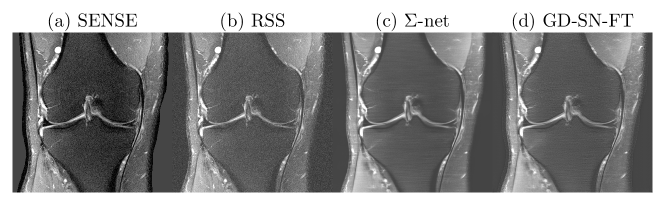

We present quantitative scores on the fastMRI validation set in Tab. 1 and qualitative results on a PDFS case for in Fig. 1. The ensembled -net achieves the best SSIM scores. While the scores of SN-FT are low, it appears most textured and sharp compared to the ensembled -net result.

Although RSS is suitable surrogate for coil combination [8], we observed, however, that the gap between RSS and sensitivity-weighted images is relatively large for PDFS cases due to Rician bias of noise (see Fig. 1). To bridge this gap, we trained a STL based on a SN with initial features. The STL was trained on the SSIM loss for 10 epochs using RMSProp (learning rate ).